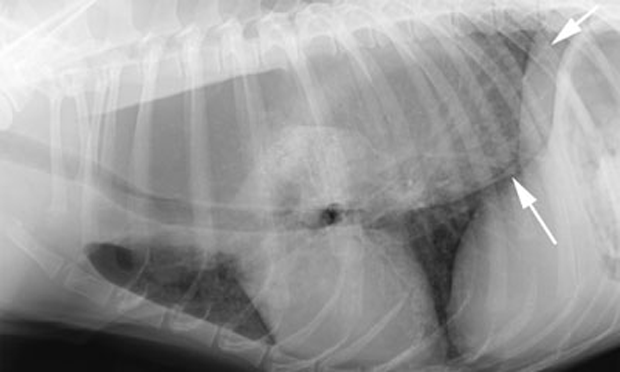

2 Year Old FS Mixed Breed Veterinary Diagnostic Imaging College of Veterinary Medicine University of Florida